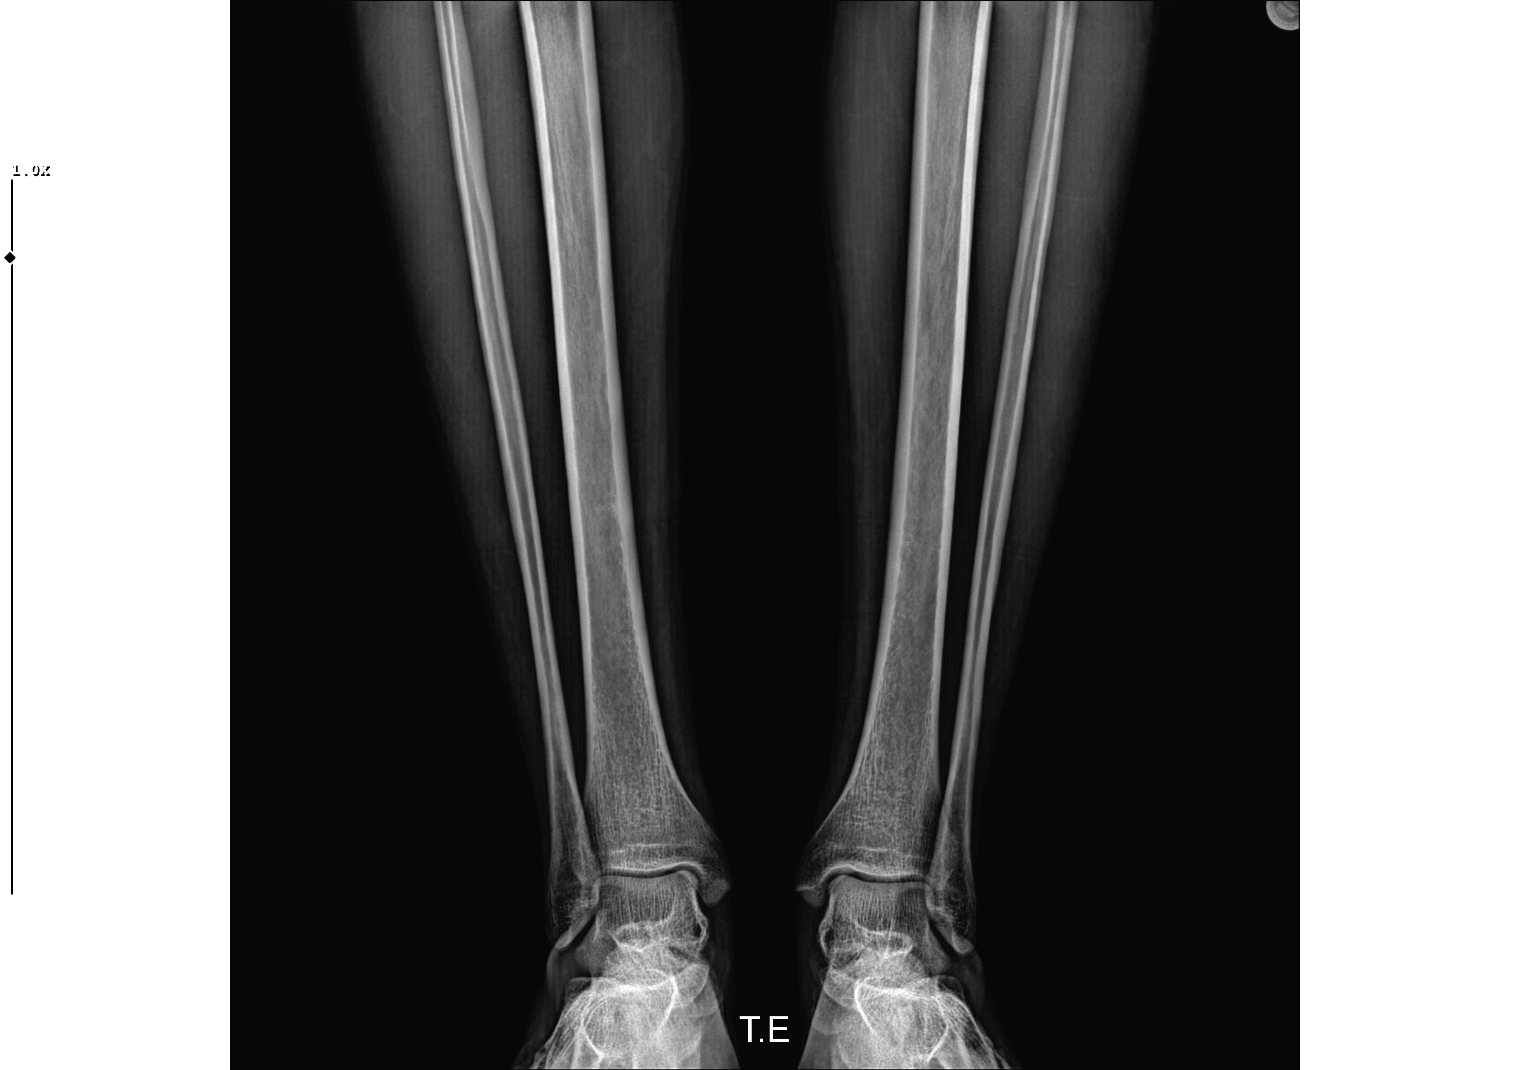

Bu xrayi 3 ay önce aldım 1.5-2 cm uzadım 177'yim şuan. Amcalarım 182 civarı baba tarafından kuzenlerim anneleri kıa olmalarına rağmen benden uzun. Annem 170 babam 180. Anne tarafım baya uzun dayılar kuzenler hepsi 190+. Kafayı yiyorum sülalenin en kısasıyım dışarıda annesi 155 babası 165 olup benden uzun olan insanları görünce dayanamıyorum. Fazlasında da göz yok 183'e ulaşsam yeter. Koltuk altı kıllarım 1 senedir çıkıyor sakal yok daha yeni yeni şakaklarda çene altında tüylenme hissediyorum ama uzamıyorlar ve gözükmüyorlar bile.

Knk epifiz plaklarina baktırman daha doğru olur çünkü once epifizler kapanır sonra parmaklar omurga falan bacağa baktir doktor söyler zaten ayrıca soyle diyeyim sana yasin küçük daha muhtemelen 180-185 arasına sabitlenirsin

Açık ama kapanmasına az kalmis

Bu xrayi 3 ay önce aldım 1.5-2 cm uzadım 177'yim şuan. Amcalarım 182 civarı baba tarafından kuzenlerim anneleri kıa olmalarına rağmen benden uzun. Annem 170 babam 180. Anne tarafım baya uzun dayılar kuzenler hepsi 190+. Kafayı yiyorum sülalenin en kısasıyım dışarıda annesi 155 babası 165 olup benden uzun olan insanları görünce dayanamıyorum. Fazlasında da göz yok 183'e ulaşsam yeter. Koltuk altı kıllarım 1 senedir çıkıyor sakal yok daha yeni yeni şakaklarda çene altında tüylenme hissediyorum ama uzamıyorlar ve gözükmüyorlar bile.View attachment 4238707

doktor copefuel vermekten baska bir sey yapmiyor kemik yasima 13 dedi o gun mutluluktan havaya uctum geld forumlara dclere attim herkes max 3-4 cm diyor babamdan kisa olacam annem de kisa degil 170 diger akrabalardan bahsetmiyorum bile ortalamalaei 187-190

doktora sormaya utandimda kapalimi bi baksaniz